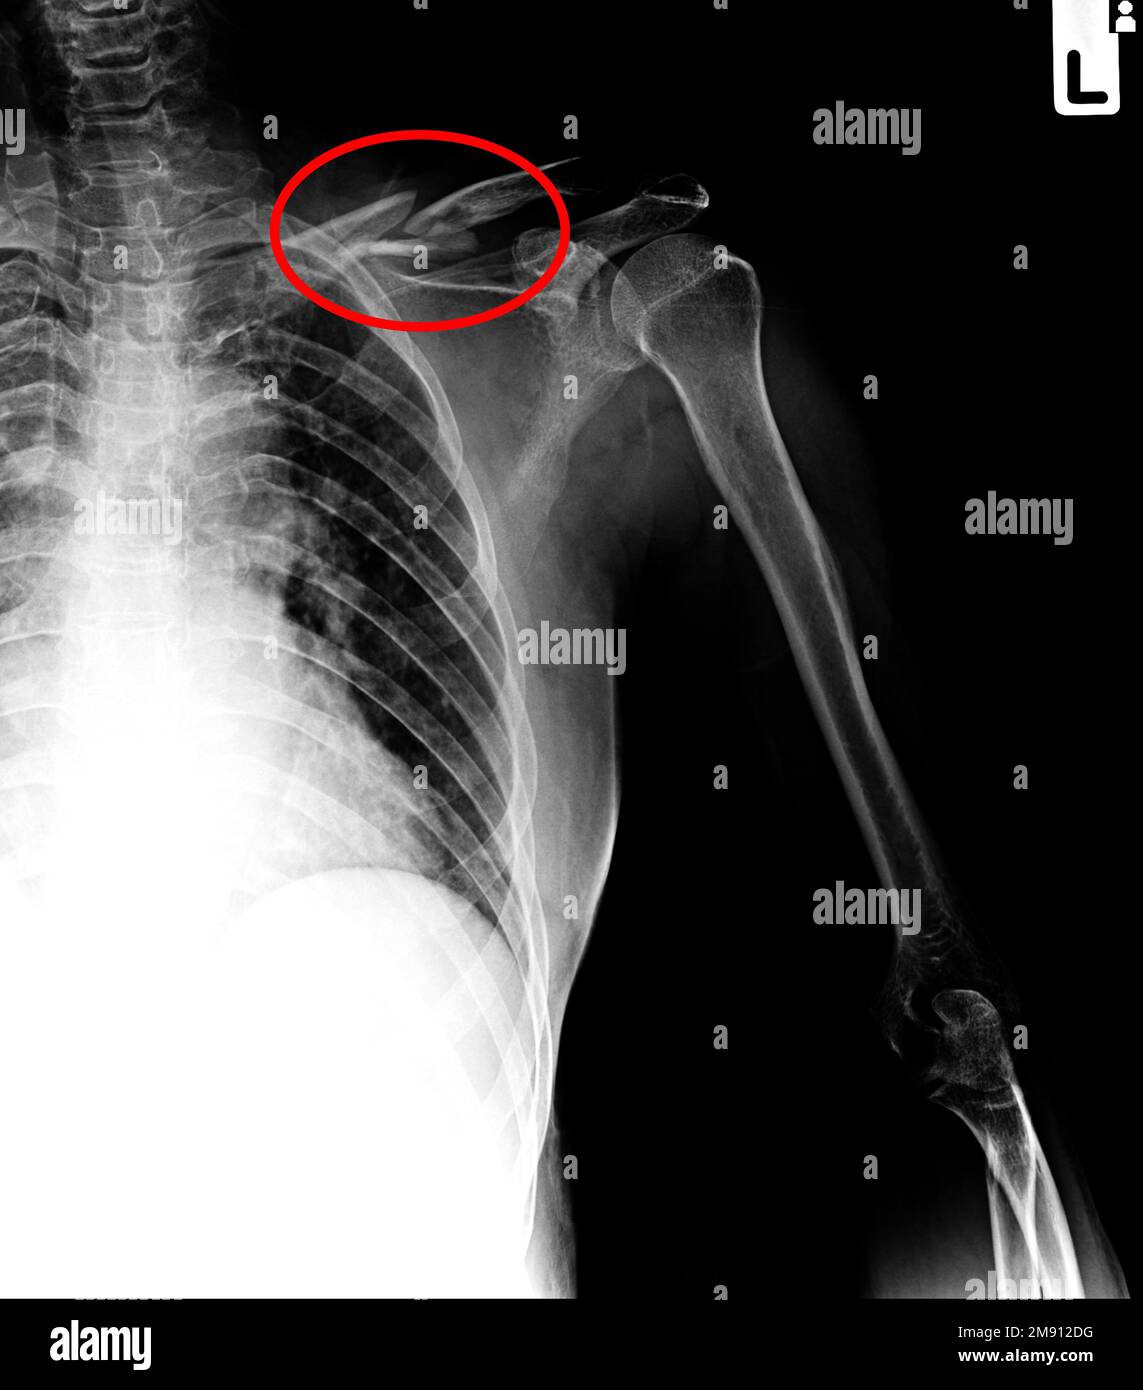

Film xray clavicle AP show fracture clavicle bone Stock Photo Alamy Clavicle Fracture X-Ray Clavicle fractures result in inferior displacement of the distal component. Note how far out of place (displaced) the broken ends of the bone are. midshaft clavicle fractures are common traumatic injuries caused by a direct impact to the shoulder girdle and is most commonly seen in. distal clavicle fractures are traumatic injuries usually caused by direct trauma to. Clavicle Fracture X-Ray.